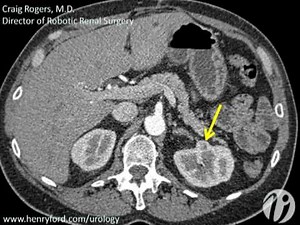

This video demonstrates the first step (operative setup) of robotic partial nephrectomy for kidney cancer. Author: Dr. Craig Rogers from Vattiikuti Urology Institute.